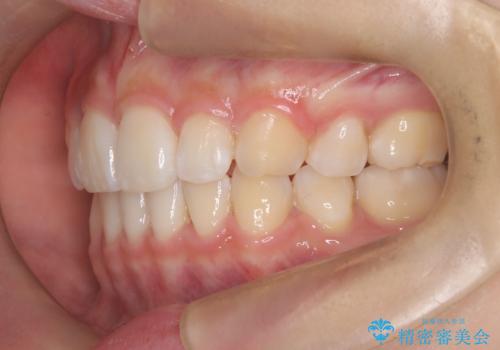

裏側矯正で口元をすっきりとした印象へ!

- ハーフリンガル

- 3年1ヶ月

- 30回以上